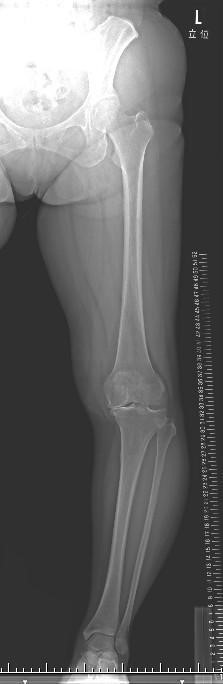

骨切り術前のレントゲン写真